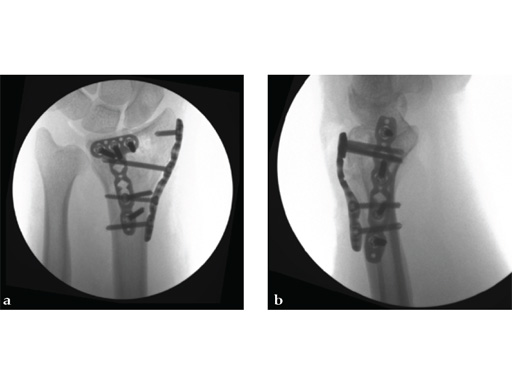

Case 1: A 62-year-old man fell on his outstretched left hand while playing tennis, sustaining an intraarticular fracture of the distal radius, Mller AO Classification 23-C3.2.

Case provided by Renato Fricker, Bruderholz, Switzerland